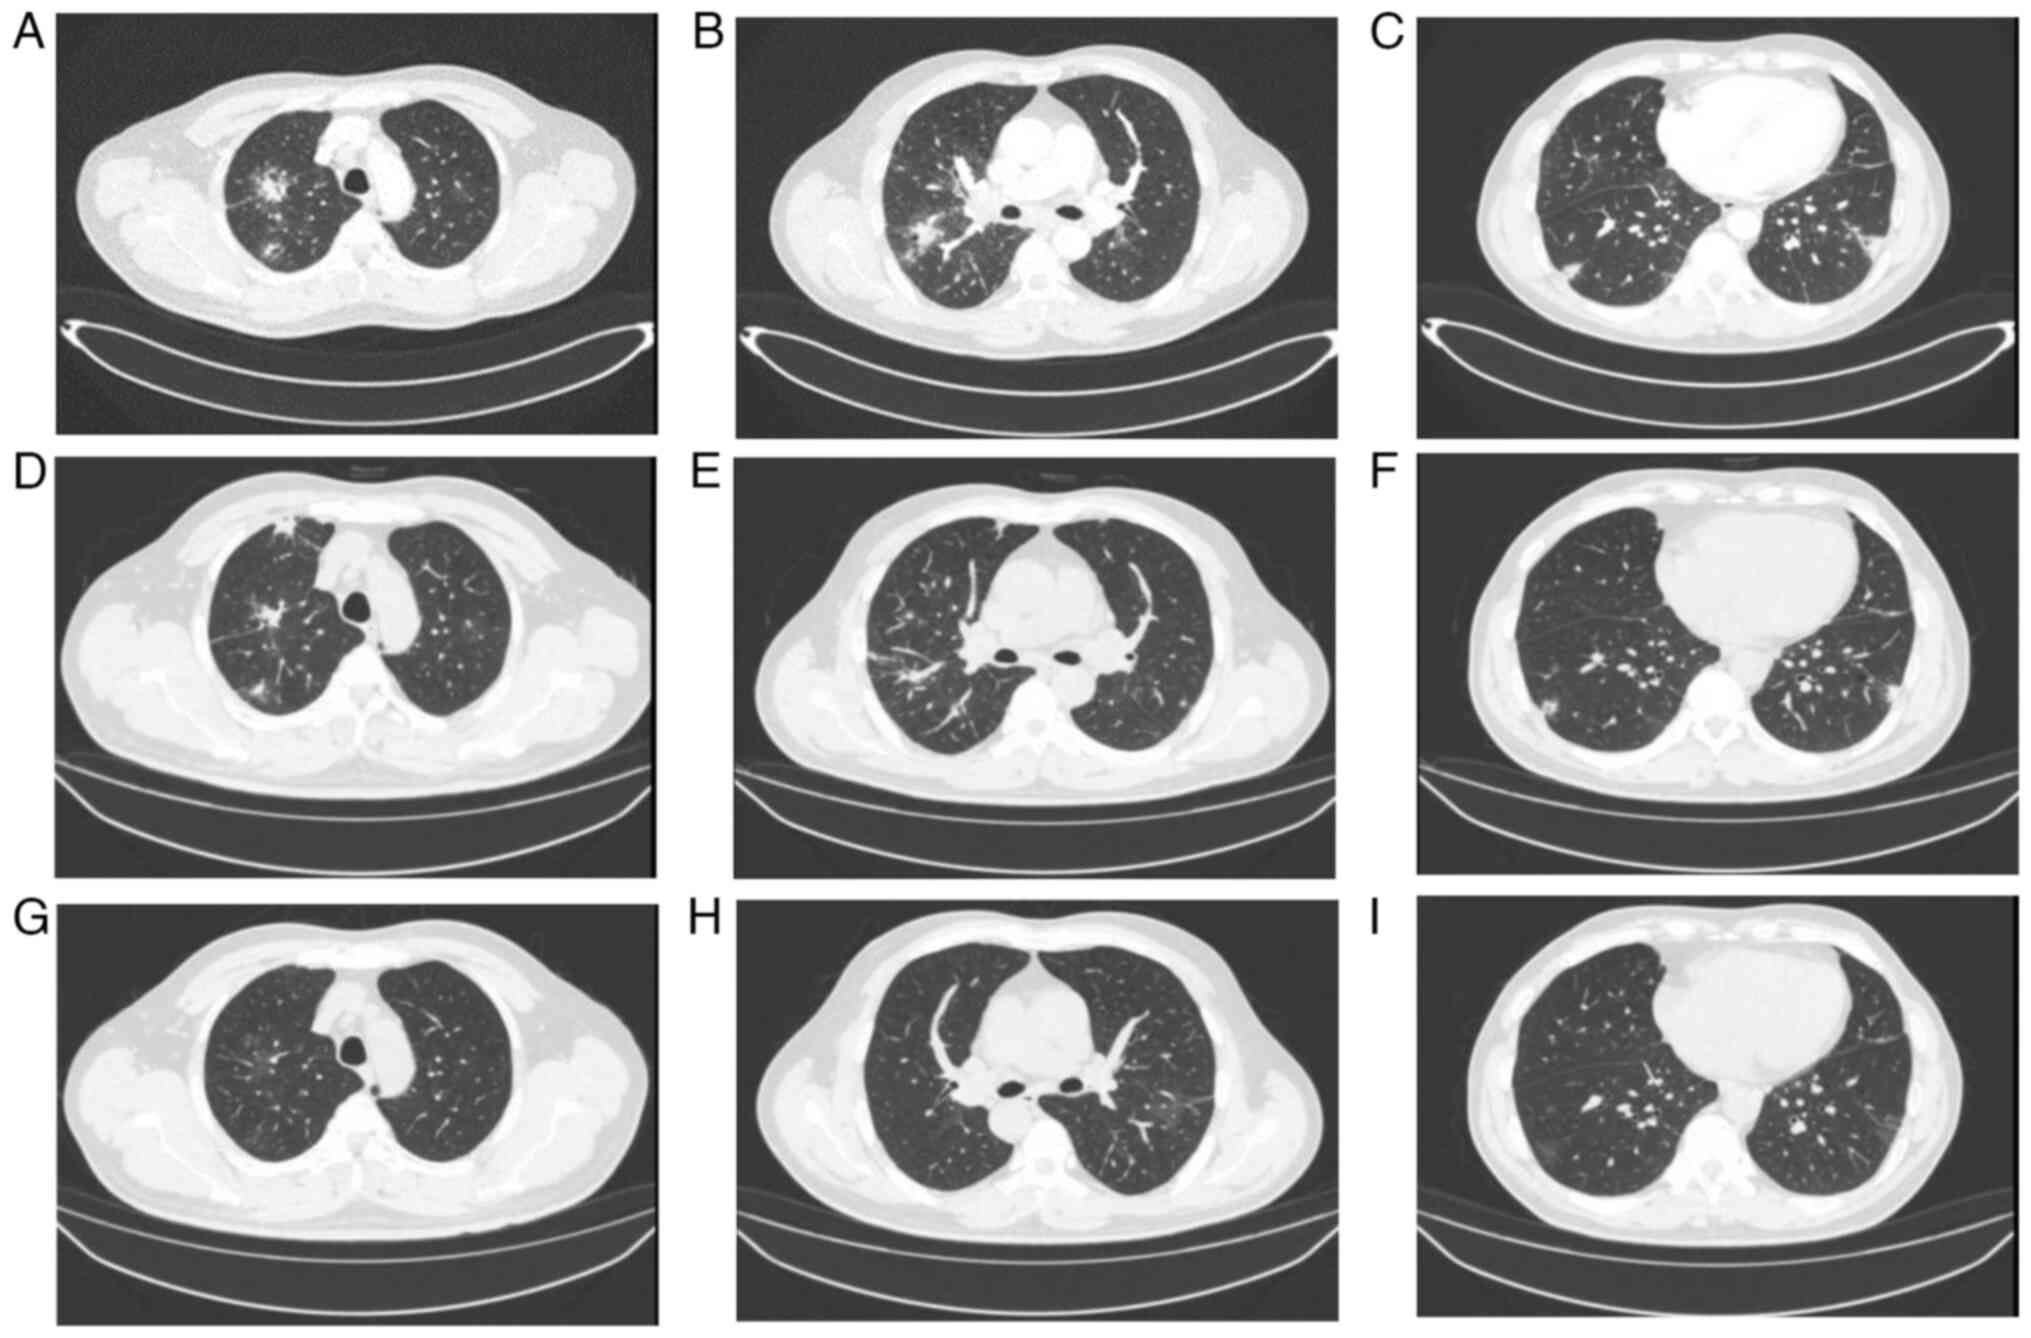

At 6 days post-admission, a chest CT (Fig. 2A-C) suggested scattered inflammation and nodules in the upper lobes of both lungs and the lower lobe of the right lung. The results of metagenomic second-generation sequencing (mNGS) and other relevant laboratory tests are presented in Table II. The initial diagnosis was critical bronchial asthma, type II respiratory failure, WD and influenza A.

Figure 2

Comparison of chest CT in patient 2. (A-C) Chest CT in March 2023. (D-F) Chest CT in April 2023. (G-I) Chest CT in August 2023. The lesions were more clearly absorbed in August compared with in March.

Subsequent review of the chest CT in April 2023 (Fig. 2D-F) and August 2023 (Fig. 2G-I) showed significant improvement of the lesion.